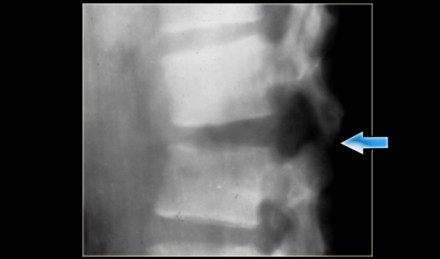

On the left images of a 21-year-old female who presented after sustaining a seatbelt type injury.

She had an exploratory laparotomy for repair of a ruptured duodenum.

There was no neurologic deficit.

First study the images, then continue reading.

What we see is a classic example of a chance fracture,

which is a three column injury with a horizontal orientation of the

fracture.

Continue with the CT-images.

What is unique about the Chance fracture is the

horizontal orientation, which is nicely demonstrated on the sagittal

reconstructions on the left.